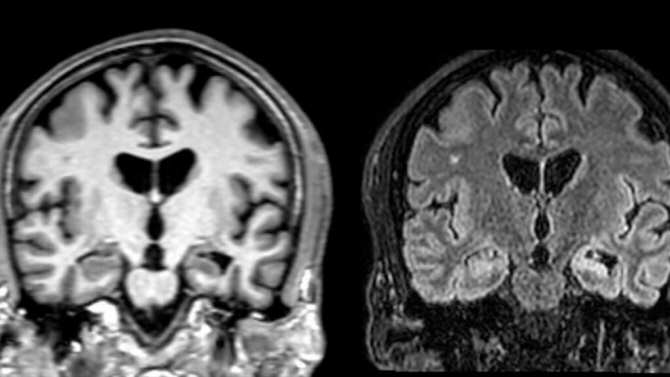

Escaneo cerebral. (Imagen: IDIBELL)

En paralelo a la validación del test, el estudio intenta correlacionar los distintos perfiles de apatía con la activación de determinadas regiones cerebrales a partir de neuroimagen. Los resultados muestran que anatómicamente la apatía está relacionada con redes motoras, cognitivas y límbicas, y que existe cierta correspondencia entre los distintos perfiles y la activación de determinados ganglios corticales y subcorticales. La Dra. Estela Càmara concluye que «estos descubrimientos incentivan profundizar en el estudio de los subtipos de apatía para identificar dianas terapéuticas personalizadas en trastornos neurológicos además de la enfermedad de Huntington».